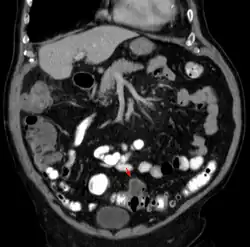

Tomografia komputerowa wykonywana jest z podaniem środka kontrastowego. Typowymi zmianami są symetryczne, zapalne zgrubienie ściany jelita grubego, rozległe nacieki tkanki tłuszczowej okołojelitowej, nagromadzenie płynu w krezce esicy i nastrzyknięcie naczyń w krezce esicy. Czułość badania ocenia się na 95%, swoistość na 35%[24]. Tomografia komputerowa ma również duże znaczenie w rozpoznaniu powikłań jak: ropnie okołojelitowe, stany zapalne otrzewnej, przetoki, i niedrożność jelit.

Obraz CT Niezmienione uchyłki esicy

Obraz CT Mały ropień w jamie brzusznej spowodowany stanem zapalnym uchyłków

Obraz CT Stan zapalny uchyłków i ropień w jamie brzusznej